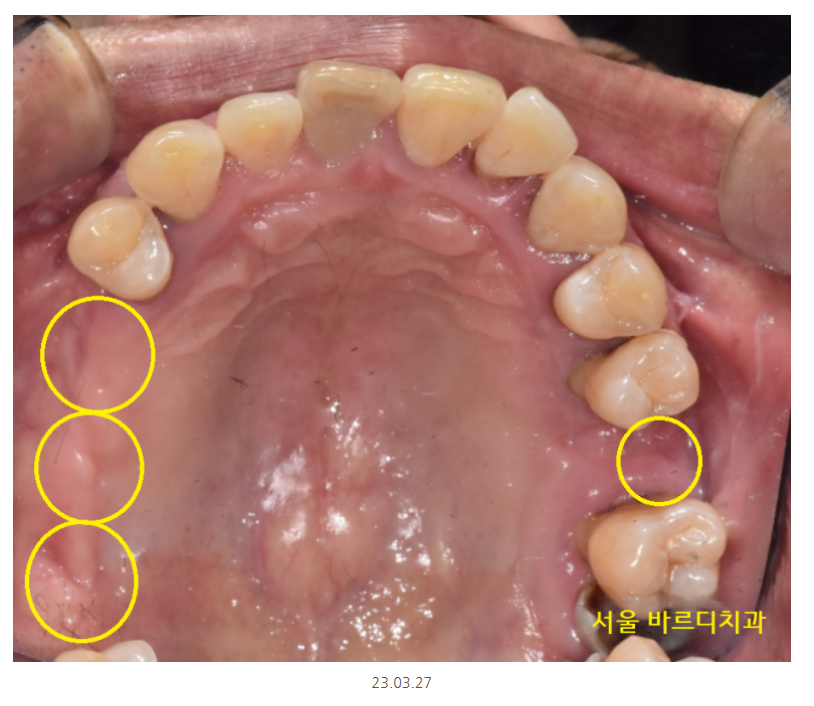

윗니는 개수로만 4개 없음

아랫니는 2개 없음

윗니 어금니 부분 예시를 보여드리면..

어금니 대부분이 잇몸뼈가 거의 없어서

뿌리만 잡고 있는 정도였거든요~

잇몸뼈가 많이 없는 상악의 경우

발치 후 뼈이식 하고 기다리다

임플란트를 심기도 하였습니다.